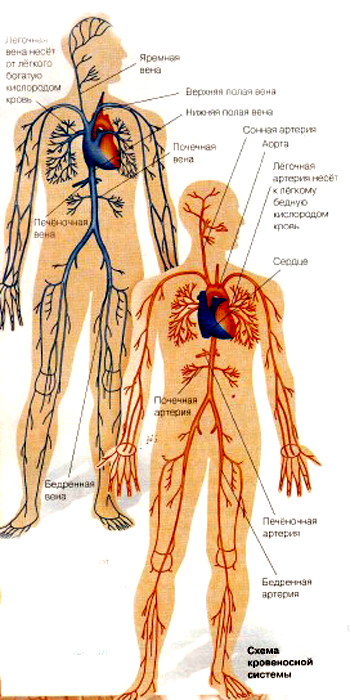

Кровеносная система человека: структура и функции